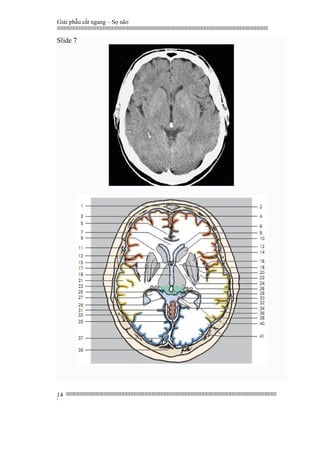

Slide 7

1. Frontal bone

2. Frontal sinus

3. Falx cerebri

4. Superior frontal gyrus

5. Cingulate gyrus

6. Middle frontal gyrus

7. Corpus callosum (genu)

8. Lateral ventricle (anterior horn)

9. Internal capsule (anterior limb)

10. Caudate nucleus (head)

11. Parietal bone

12. Inferior frontal gyrus

13. External capsule

14. Putamen

15. Septum verum (precommissural septum)

16. Cistern of lateral cerebral fossa

(insular cistern)

17. Hypothalamus

18. Internal capsule (genu)

19. Third ventricle

20. Claustrum

21. Superior temporal gyrus

22. Extreme capsule

23. Temporal bone

24. Globus pallidus (pallidum)

25. Geniculate body

26. Internal capsule (posterior limb)

27. Hippocampus

28. Thalamus

29. Parahippocampal gyrus

30. Pinealgland (calcified)

31. Tentorium cerebelli

32. Quadrigeminal plate (colliculus)

33. Vermis of cerebellum

34. Quadrigeminal and ambient cisterns

35. Straight sinus

36. Middle temporal gyrus

37. Superior sagittal sinus

38. Lateral ventricle (trigone)

39. Occipital bone

40. Parietal bone

41. Occipitalgyri

1. Xương trán

2. Xoang trán

3. Liềm não

4. Hồi trán trên

5. Hồi viền

6. Hồi trán giữa

7. Gối thể chai

8. Sừng trước não thất bên

9. Chi trước bao trong

10. Đầu nhân đuôi

11. Xương đỉnh

12. Hồi trán dưới

13. Bao ngoài

14. Bèo sẫm

15. Mép não lớn

16. Bể hố não bên

(bể thuỳ đảo)

17. Dưới đồi

18. Gối bao trong

19. Não thất ba

20. Nhân trước tường

21. Hồi thái dương trên

22. Bao cực ngoài

23. Xương thái dương

24. Bèo nhạt

25. Thể gối

26. Chi sau bao trong

27. Hồi hải mã

28. Đồi thị

29. Hồi cạnh hải mã

30. Vôi hoá tuyến tùng

31. Lều tiểu não

32. Mãnh củ não sinh tư (lồi củ)

33. Vòm tiểu não

34. Củ não sinh tư và bể TM lớn

35. Xoang thẳng

36. Hồi thái dương giữa

37. Xoang tĩnh mạch dọc trên

38. Vùng tam giác não thất ba

39. Xương chẩm

40. Xương đỉnh

41. Hồi chẩm